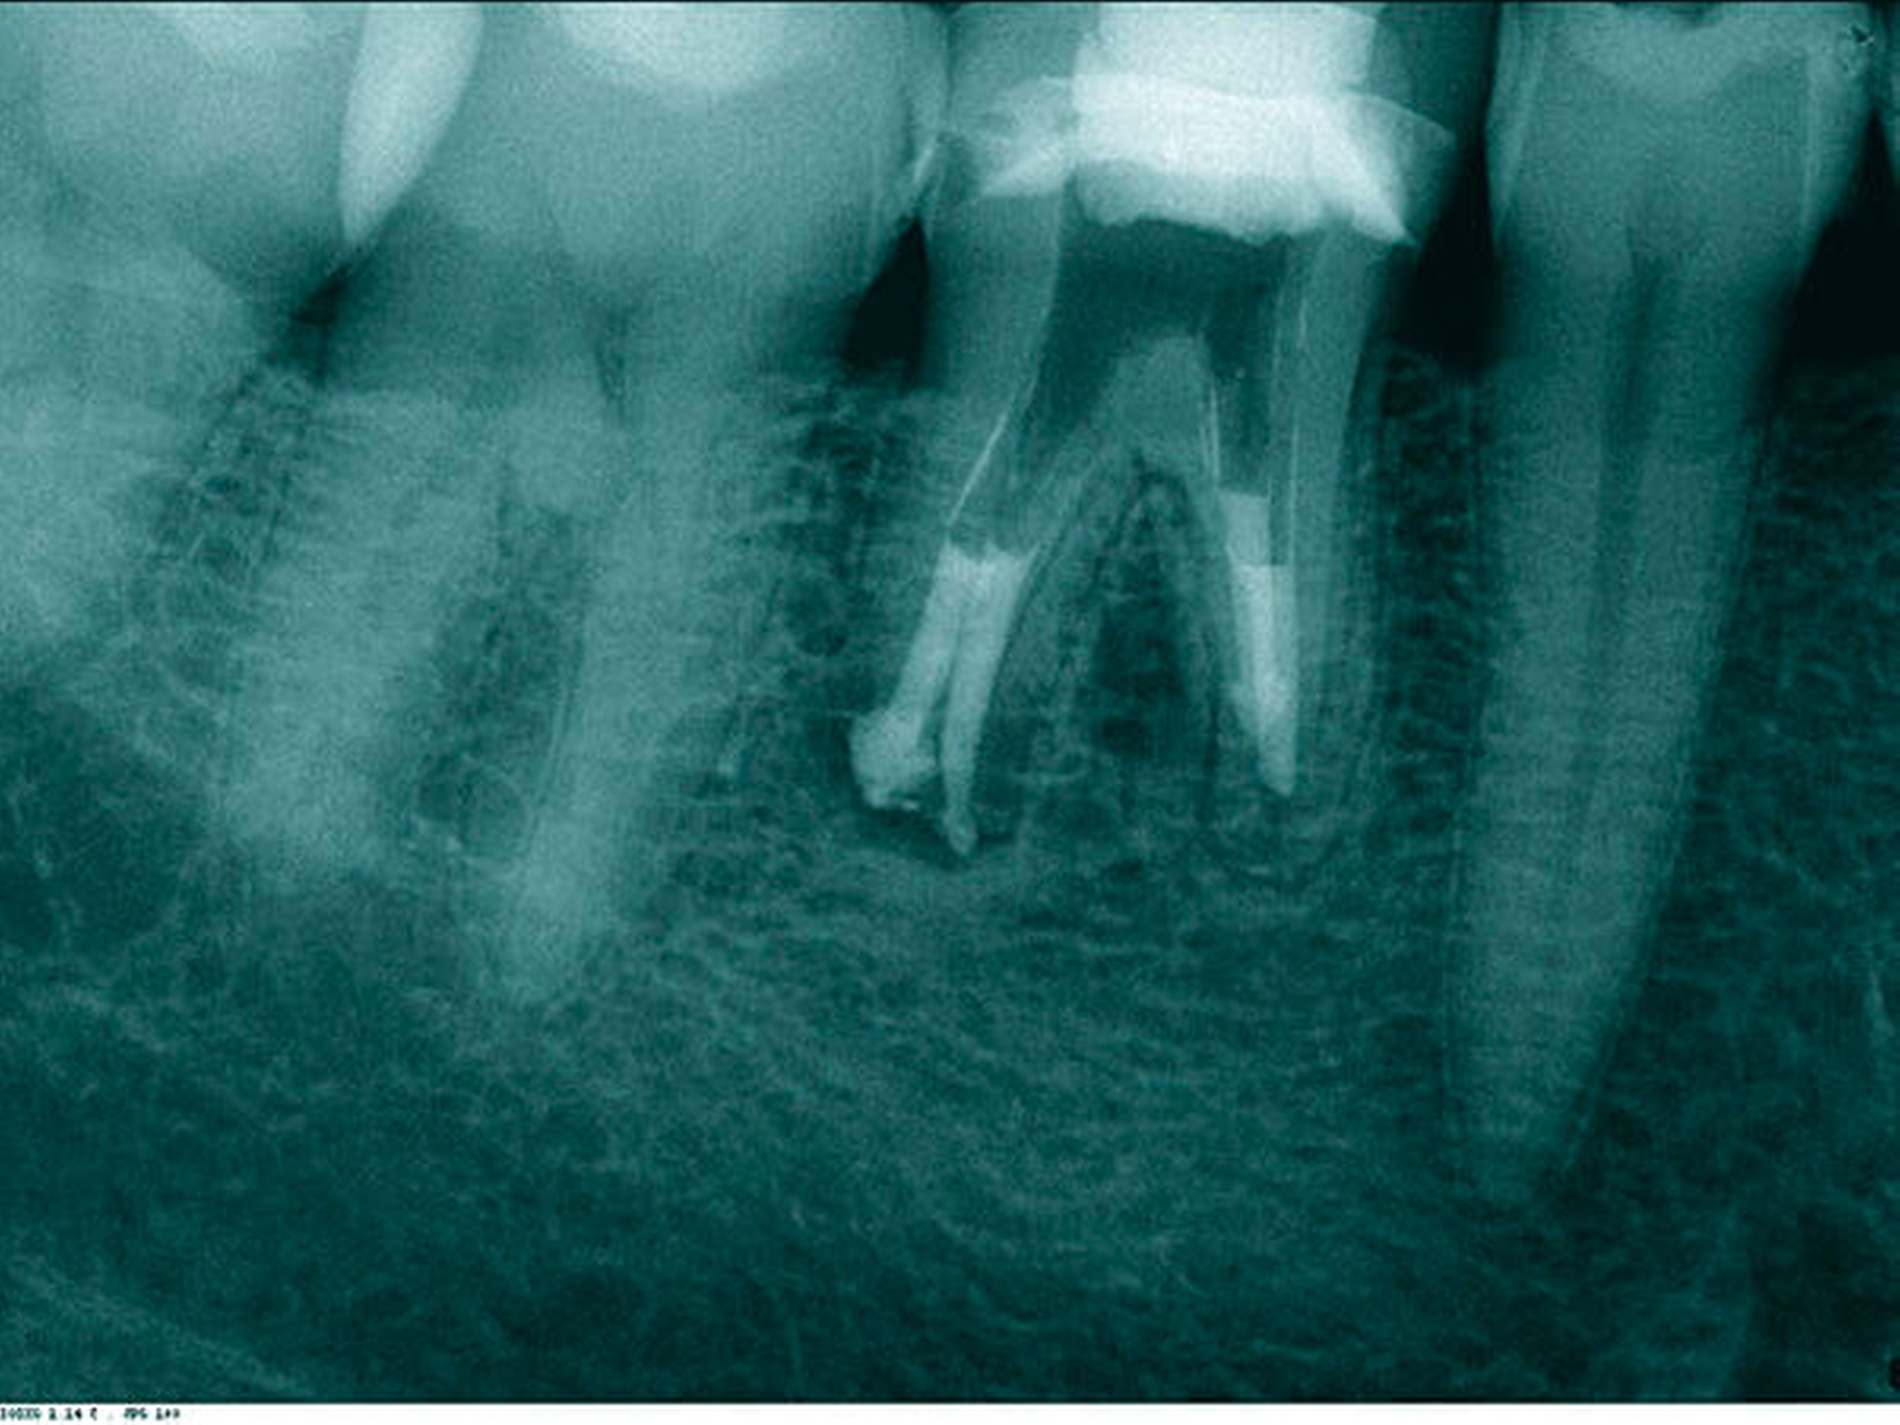

In der ersten Sitzung erfolgten die Trepanation des Zahnes 46 und die komplette Entfernung der Guttapercha unter Kofferdam (Abbildung 11). Nach ausgiebiger Desinfektion mit NaOCl 5 Prozent und EDTA 17 Prozent sowie Schallaktivierung mittels EDDY-Spitzen erfolgte eine medikamentöse Einlage mit AH Temp. In der zweiten Sitzung wurden nach der endometrischen Ermittlung der Arbeitslänge (mesiobukkal 15 mm, mesiolingual 14 mm und distal 13,5 mm) die Kanäle manuell bis ISO 70 aufbereitet. In alle drei Kanäle wurden dann apikale Plugs mit ProRoot MTA (DentsplySirona, Bensheim) eingebracht und diese radiologisch kontrolliert (Abbildung 12). Im Anschluss wurden die koronalen Kanalanteile und die Zugangskavität mit dual-härtendem Komposit verschlossen. Danach wurde die orthograde Revision an Zahn 47 durchgeführt, wobei der anresorbierte distale Kanal ebenfalls mit MTA verschlossen wurde. Abbildung 13 zeigt die Kontrollaufnahme der beiden Zähne nach der Behandlung. Die Nachkontrollen nach neun und 18 Monaten zeigen einen deutlichen Rückgang der Läsionen (Abbildungen 14 und 15) und die Zähne waren symptomfrei. Jedoch kam es zu einer Zunahme der distalen parodontalen Tasche an 46.